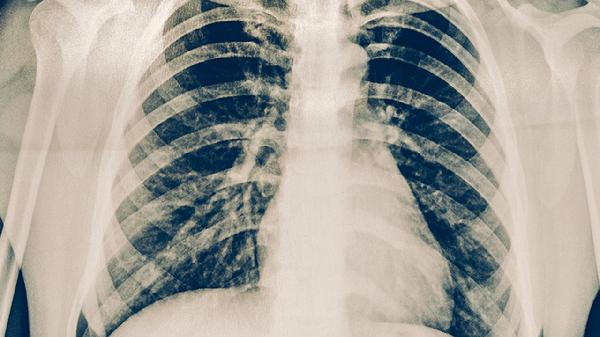

肺结核患者用药期间应保持高蛋白饮食如鸡蛋、鱼肉,避免酒精及肝毒性食物。适当进行散步等低强度运动增强体质,但需避免过度消耗体力。所有药物调整必须由专科医生根据检查结果决定,不可自行增减剂量或停药。治疗全程需配合痰检及影像学复查,确保疗效与安全性平衡。